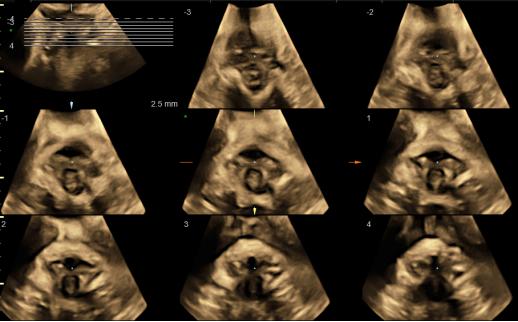

梦想系列煊光E8优异的基础图像质量、创新的容积成像模式和分析处理技术,诸如:SRI II斑点噪声抑制成像、CrossXBeam CRI实时空间复合成像、HD-Flow超高细微分辨血流成像技术、HDlive高分辨容积成像技术、VCI高级容积对比成像模式和OmniView自由解剖成像、TUI断层超声显像等创新技术结合专业的自动化成像与诊断工具SonoRenderlive实时自动胎儿追踪成像、SonoNT自动胎儿颈后透明层厚度测量、SonoIT自动胎儿颅内透明层测量、SonoBiometry自动胎儿生长指标测量等。上述技术为产前超声筛查与诊断提供了业绩最完整的系统解决方案。

OmniView自由解剖切面成像——通过简单划线方式对3D/4D图像进行切割,包括直线、曲线、自由曲线以及折线四种模式,主要应用于二维无法获取的不规则组织的切面。

梦想系列煊光E8先进的探头技术、高品质的基础图像、以及一整套先进的胎儿心脏成像技术来评估胎儿心脏结构和功能,基于革命性的腔内探头技术,将早孕期胎儿心脏检查带入前所未有的水平,分析方法和流程包括:高级STIC (时间空间相关成像) 包括SonoVCAD heart新优势 (胎儿心脏计算机辅助诊断)和STIC M型技术,高级STIC结合B-Flow成像,Z-Score 评价胎儿心脏结构生长的定量工具,包括评估先天性胎儿心脏异常的定量分析,用于高质量的胎儿心脏专项检查。